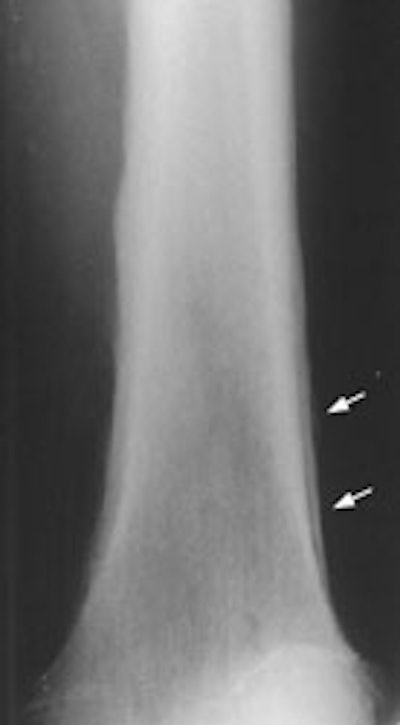

New Criterion for Determination of Pathologic Hilar Adenopathy

Example 2: This patient is an example of a false negative CT for hilar nodal metastases even when applying the suggested new criterion. The patient had a peripheral adenocarcinoma in the left upper lobe (black arrows). The left hilar node (yellow arrows) is not pathologic by size criteria, nor does it exhibit a convex margin with the adjacent lung parenchyma. This is a normal node by CT, however, at histopathologic analysis the node was positive for malignant cells.

NOTE: Click image to enlarge